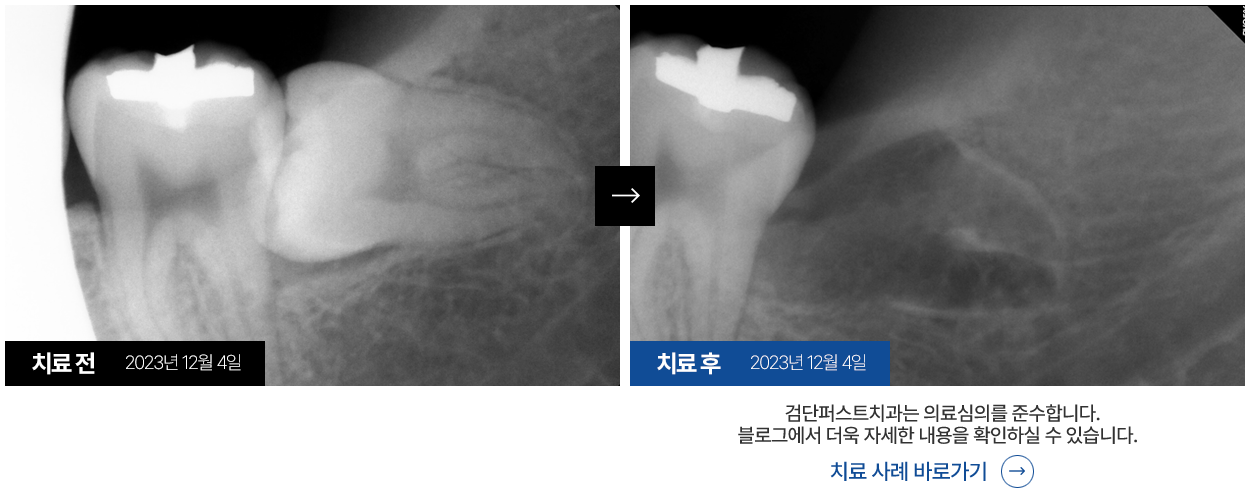

사랑니발치는 간단해 보일지라도 어려운 치료로, 발치 경험이

많은 대학병원 전문의에게 발치받으시는 것이 좋습니다.